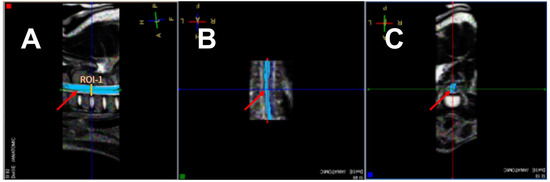

2.3. MR Imaging and DTI Protocol

2.4. Image and DTI Analysis